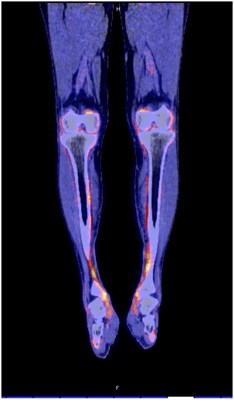

8. Гипертрофическая легочная остеоартропатия (ГЛО)

ГЛО, или синдром Мари-Бламбергера, представляет собой классическую костно-мышечную паранеоплазию и часто описывается в ревматологической литературе. Синдром характеризуется двумя отличительными симптомами: одним из них является утолщение дистальных фаланг пальцев рук и/или пальцев ног в виде барабанных палочек, а другой — воспалительный пролиферативный периостит, вызывающий костные и суставные боли, а иногда и синовит с выпотом в полости сустава. Преобладающими локализациями являются большеберцовая и малоберцовая кости, коленные и голеностопные суставы (Рис. 3). Это периостальное воспаление вызывает активацию остеобластов, что легко обнаруживается благодаря усиленному поглощению контраста при остеосцинтиграфии и оссификации надкостницы вдоль трубчатых костей при обычной рентгенографии. При ретроспективном анализе частота ГЛО при первичном раке легкого была близка к 1 %, однако ГЛО иногда также может возникать и при других типах злокачественных новообразований (преимущественно внутригрудных). Из-за характерной акральной активации фибробластов и периостальной активации остеобластов этот синдром первоначально считался вариантом акромегалии. Сегодня стало ясно, что тромбоцитарный фактор роста (PDGF) или фактор роста эндотелия сосудов (VEGF), продуцируемые опухолевыми клетками, могут способствовать развитию ГЛО.

Рисунок 3. ПЭТ КТ показывает значимое поглощение 18 F-флюородеоксиглюкозы вдоль контуры большеберцовой кости у пациента с ГЛО и аденокарциномой бронхов.